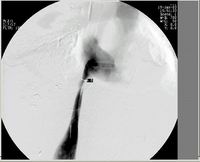

图A:支架植入前DSA造影,见下腔静脉近入心房处受压梗阻,最狭窄处0.6厘米。

图B: 支架植入前DSA造影,见下腔静脉近入心房处受压梗阻,远端高度扩张。

图C: 大C臂电视下准确定位后植入支架,梗阻解除,血液顺利通过,原最狭窄处扩大至1.5厘米。

图D: 支架植入后,支架定位准确,支架扩张无移位,下腔静脉梗阻解除,双下肢水肿开始消退。